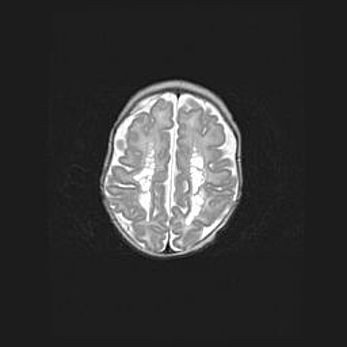

Церебральная ишемия II.

Возраст: 5 дней

Вес: 3400 г

Пол: женский

Окружность головы: 35 см

Срок гестации: 39 недель

Церебральная ишемия – это заболевание, характеризующееся недостаточностью (гипоксией) либо полным прекращением (аноксией) снабжения мозга кислородом по причине закупорки одного или нескольких сосудов. Это приводит к  что метаболическим расстройствам различной степени тяжести в тканях головного мозга, развитию коагуляционных некрозов и гибели нейронов.